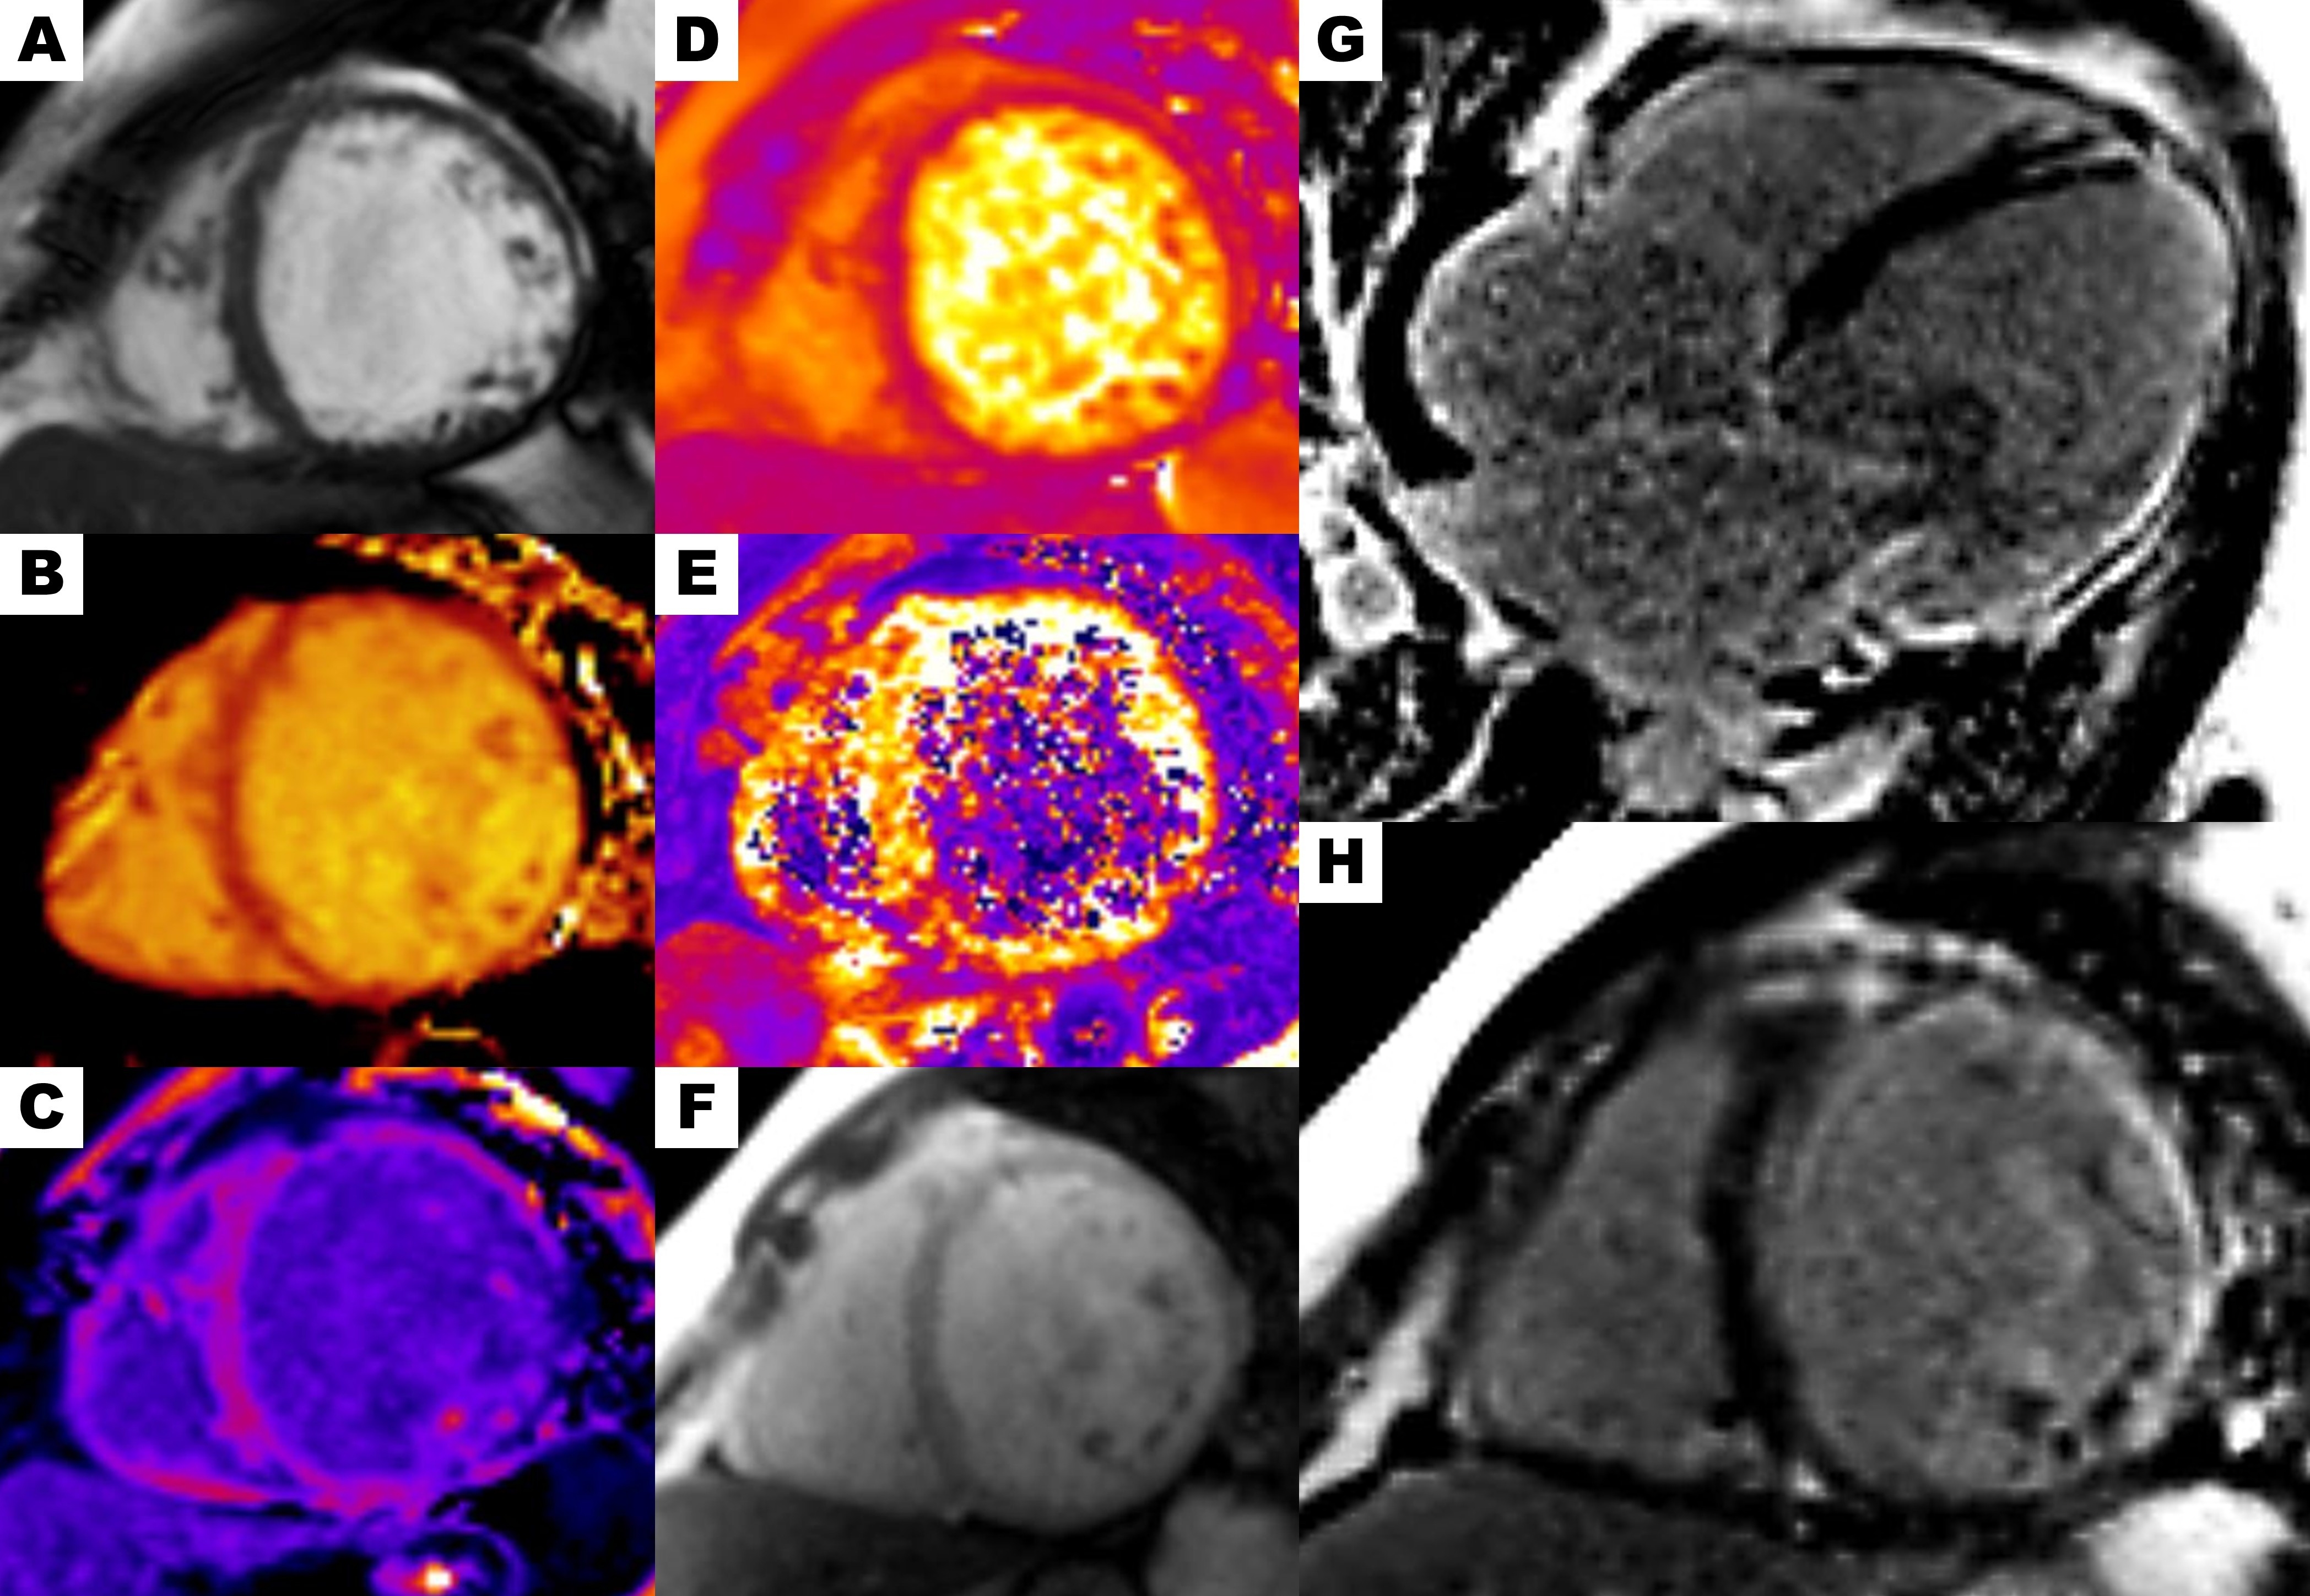

Figure 2. Cardiac magnetic resonance. (A) Balanced steady-state free precession cine short-axis view. (B) Elevated native T1 mapping values in the lateral wall across all three segments (1,124 ms). (C) Post-contrast T1 mapping showing an extracellular volume of 38%. (D) T2 mapping within the normal range. (E) T2* mapping within the normal range. (F) Short-axis first-pass perfusion demonstrating normal myocardial perfusion. Phase-sensitive inversion-recovery sequence showing LGE with transmural enhancement in the anterior, lateral, and inferior walls: (G) Four-chamber view, (H) Short-axis view.